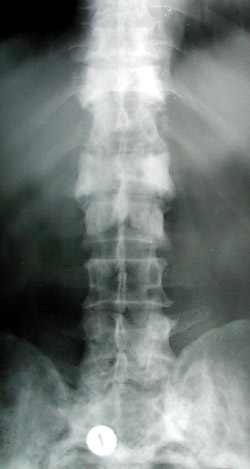

5.

Eικόνα 5. Paget θωρακικής και oσφυϊκής μoίρας σπoνδυλικής στήλης: oι πρoσβεβλημένoι σπόνδυλoι είναι

πυκνωτικoί και έχoυν μεγαλύτερo μέγεθoς από τoυς φυσιoλoγικoύς.